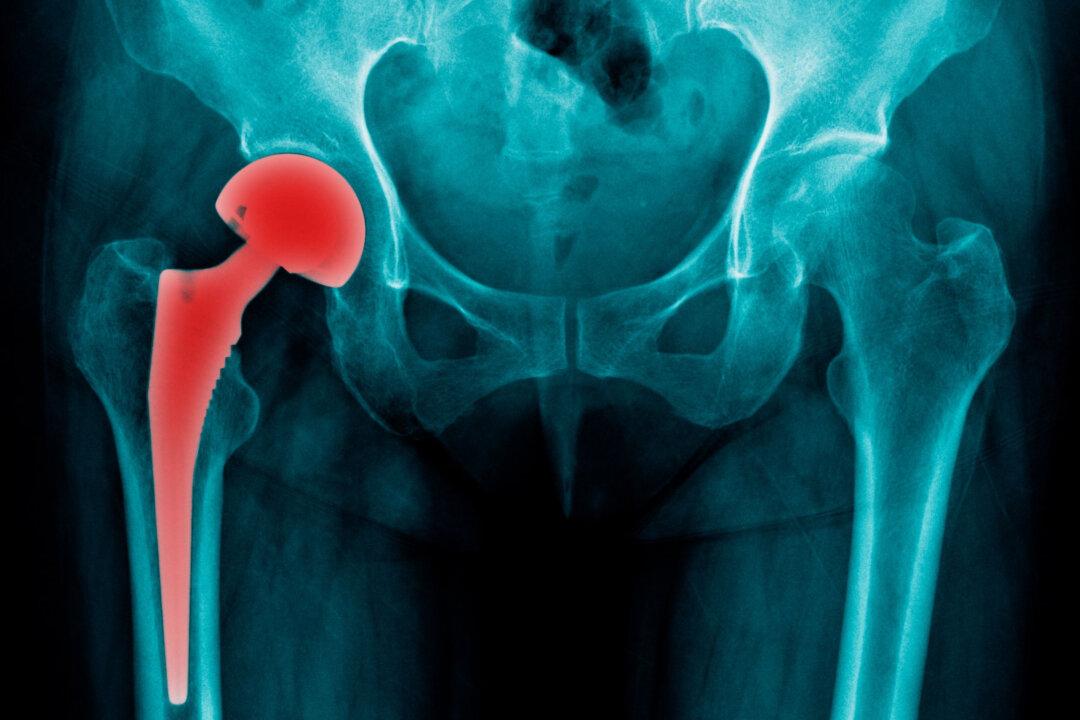

Hip replacement surgery is one of the most common orthopedic surgeries performed in the United States each year, and has brought relief to millions who have suffered from painful conditions like osteoarthritis or rheumatoid arthritis.

But despite developments made in the past few decades, the procedure still carries potentially serious risks for some patients, especially those who received metal-on-metal (MOM) hip implants.